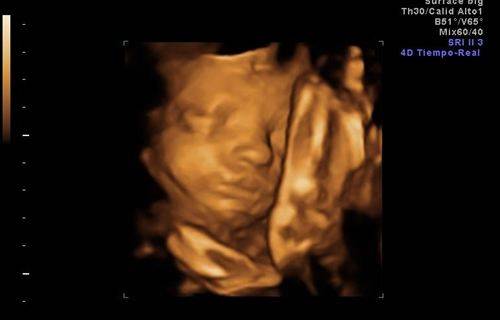

Un artículo publicado en Proceeding of the National Academy of Sciences ha revelado que los bebés podrían desarrollar la habilidad del lenguaje antes de su nacimiento. En una gestación de 28 semanas los científicos han concluido que los bebés diferencian las silabas «ga» y»ba», así como las voces mas

culinas de las femeninas. Los expertos ya estaban de acuerdo en que los bebés son capaces de escuchar ruidos en el vientre a partir de la semana 23, sin embargo todavía se discute si los seres humanos nacen con la habilidad innata de procesar el habla o si es algo adquirido. Los autores del estudio presentado en PNAS explican que los factores ambientales son importantes, pero que los procesos lingüísticos parecen innatos en el ser humano. La Gaceta.